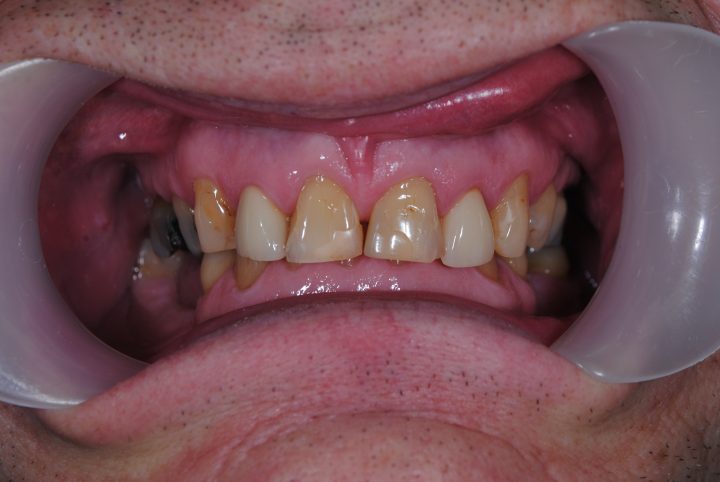

Garreth ist ein englischer Synchronisationsschauspieler. Der Zustand seinen Zähnen hat die Lautbildung und seinen Gesundheitszustand schon seit langem gestört.

Wegen seiner Arbeit war die herausnehmbare Prothese ausgeschlossen, weil die Lautbildung und die Sprache sich verändern würden.

Zu gleicher Zeit wurden die obere, zweiseitige Knochenaufbau und die obere Implantation im Kauen Region durchgeführt. Auf beiden Seiten haben wir schweizerische Straumann Implantate, Premium Qualität benutzt.

Er hat unten, in die Kauenregion 2-2 Implantate bekommen. Nach der 6 Monate lange Heilungszeit wurden metallfreie Zirkonkronen auf den Frontzähnen bearbeitet, und auf Implantate Metallkeramik Kronen hergestellt.